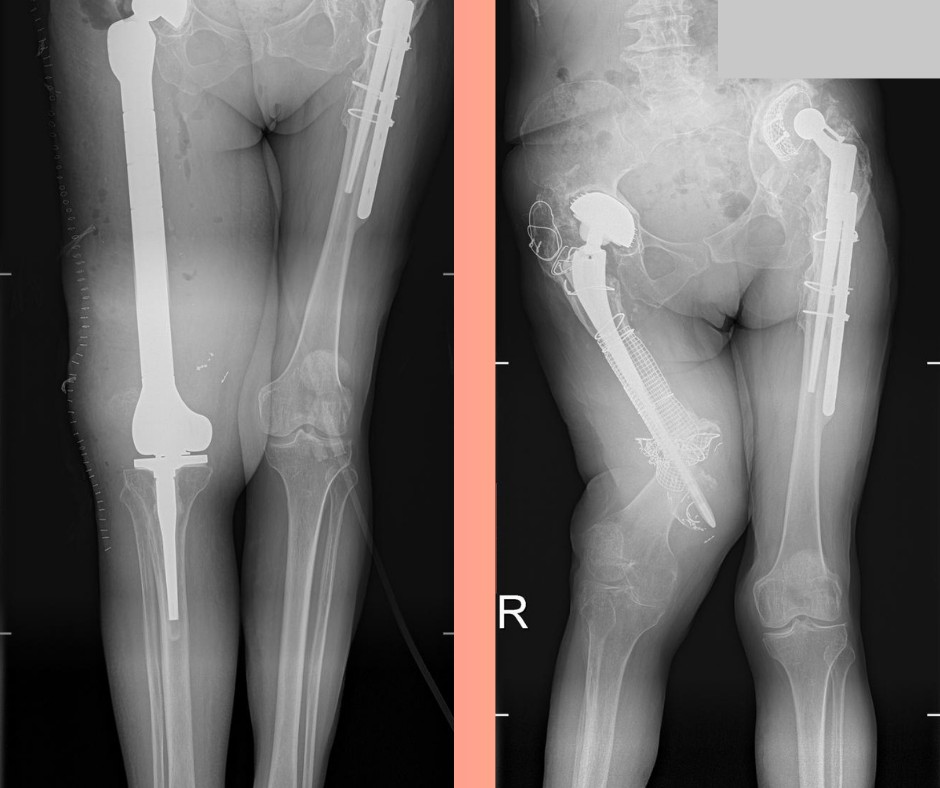

- Wykonaliśmy zabieg, który niewiele ośrodków w Polsce wykonuje – przyznaje lek. Paweł Olszewski z Kliniki Ortopedii, Traumatologii i Chirurgii Ręki USK, który był głównym operatorem. – Była to operacja jednoczasowej wymiany stawu biodrowego i kolanowego wraz z wstawieniem implantu kości udowej.

Lekarze odpreparowali i usunęli zniszczoną kość udową, a na jej miejsce wszczepili sztuczna kość tytanową. Do tego wymienili endoprotezę stawu biodrowego i kolanowego. Najczęściej takie rozwiązania są proponowane pacjentom nowotworowym, przy dużych ubytkach kości. W tym przypadku zastosowano specjalny system, który działa na zasadzie „klocków”. Lekarze tak dobierają poszczególne elementy, by odwzorować naturalne stawy i kości. Operacja trwała 3,5 godziny. Przeprowadziło ją 4 chirurgów.